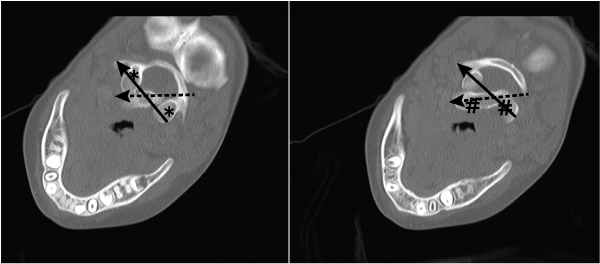

On Day 11, in view of ongoing neck pain and torticollis, a computed tomography (CT) scan of the patient’s neck showed rotational atlantoaxial subluxation, with C1 rotated to the right relative to C2, and persistent bilateral cervical lymphadenopathy (Box 1 and Box 2). The other feature on the CT scan was a hypodense region in the retropharyngeal area measuring 6 mm anteroposteriorly and 7.6 mm mediolaterally, possibly indicating a retropharyngeal abscess (Box 3). Intravenous cefotaxime and lincomycin were therefore continued for 14 days. The patient was placed in cervical traction for 8 days to reduce the subluxation, followed by visor orthosis (a rigid vest and collar) to immobilise her neck.

1 Three-dimensional reconstruction of a computed tomography scan showing the left lateral mass of C1 (solid arrow) with subluxation relative to the lateral mass of C2 (dashed arrow)